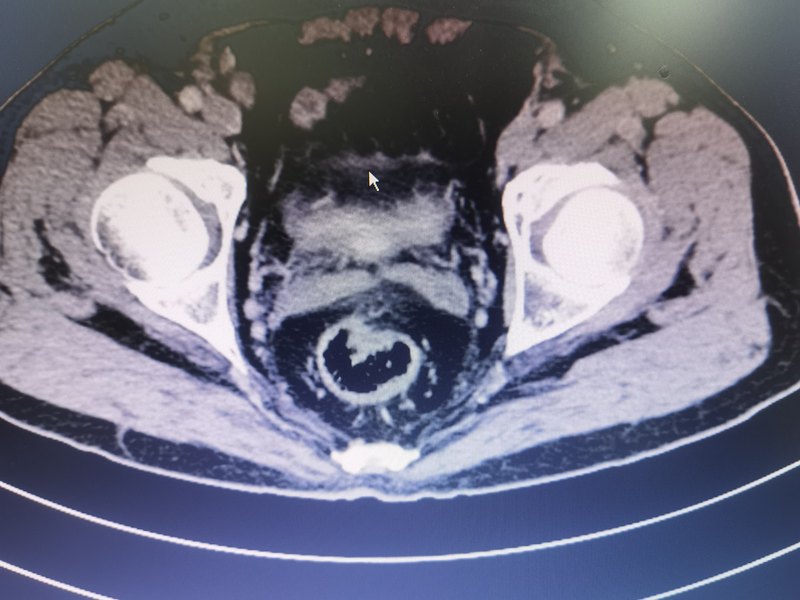

直腸癌是常見惡性腫瘤之一,近年來發(fā)病率呈上升趨勢(shì),隨著診療技術(shù)的進(jìn)步,以手術(shù)為核心的綜合治療效果不斷改善,低位保肛、改善生存已不像從前那樣困難,腹腔鏡、機(jī)器人手術(shù)等微創(chuàng)技術(shù)手段亦顯著降低了手術(shù)創(chuàng)傷,隨著一體化的深入,在院本部胃腸外科的支持下,近期胃腸外科東病區(qū)李衛(wèi)團(tuán)隊(duì)完成了一例3D腹腔鏡經(jīng)直腸取標(biāo)本(腹部無切口)直腸癌根治術(shù)(naturalorificespecimenextractionsurgery,NOSES)。這是一例中老年男性患者,因大便習(xí)慣改變2月就診,腸鏡發(fā)現(xiàn)距肛門10-15cm可見一菜花樣新生物,占管腔2/3圈,術(shù)前腹部增強(qiáng)CT提示:直腸上段腫瘤性占位,腹腔其余臟器未見明顯異常,術(shù)前活檢病理提示腺體中-重度異型增生;BMI:20.5。傳統(tǒng)上選擇開腹手術(shù),需在下腹部有一個(gè)15-20cm長(zhǎng)的切口,現(xiàn)在隨著腹腔鏡等微創(chuàng)技術(shù)的進(jìn)步,選擇腹腔鏡手術(shù)的醫(yī)生越來越多,已成為主流趨勢(shì)。腹腔鏡手術(shù)通常需要在腹壁上打5個(gè)Trocar孔(2個(gè)1cm的和3個(gè)0.5cm的),還需要在下腹部開一個(gè)5-8cm的切口將腫瘤標(biāo)本取出體外及完成消化道重建,腹腔鏡手術(shù)較開腹手術(shù)創(chuàng)傷明顯減少,術(shù)后恢復(fù)更快。在此基礎(chǔ)上是否還有更微創(chuàng)的辦法能為這位患者解除疾病呢?結(jié)合團(tuán)隊(duì)既往經(jīng)驗(yàn)和目前日益興起的NOSES手術(shù),決定為病人行3D腹腔鏡NOSES直腸癌根治術(shù)。在腹部用5個(gè)Trocar孔進(jìn)行操作,完成腫瘤根治性切除后,在保證無瘤及無菌原則下經(jīng)直腸取出標(biāo)本,然后在腹腔鏡下完成乙狀結(jié)腸直腸的吻合,手術(shù)僅耗時(shí)4個(gè)小時(shí),手術(shù)順利,術(shù)后病人恢復(fù)順利,術(shù)后第1天即恢復(fù)排氣,第二天開始飲水,逐漸過渡飲食,且術(shù)后無明顯疼痛。NOSES,即減少腹部主要的切口經(jīng)自然腔道取出標(biāo)本。NOSES取出標(biāo)本的主要自然腔道為直腸及陰道(女病人),對(duì)于直腸乙狀結(jié)腸手術(shù),可直接經(jīng)直腸遠(yuǎn)端及肛門取出標(biāo)本,對(duì)于女病人腹腔內(nèi)其他部位病變,可經(jīng)陰道取出標(biāo)本。NOSES較傳統(tǒng)腹腔鏡手術(shù)相比可顯著降低腹部切口并發(fā)癥及術(shù)后疼痛發(fā)生率,改善患者術(shù)后恢復(fù)體驗(yàn)及局部美觀程度,提升患者恢復(fù)信心,越來越多的單位與醫(yī)生在開展此項(xiàng)技術(shù)。但NOSES同樣存在其局限性和問題,比如會(huì)延長(zhǎng)手術(shù)時(shí)間,吻合器釘頭如何置入,無菌無瘤原則如何更好保證,都需要一些經(jīng)驗(yàn)和小技巧方能妥善解決。開展NOSES,需要一個(gè)完善的團(tuán)隊(duì)配合,且需要選擇合適的病例,選擇腫瘤分期較早,且腫瘤大小相對(duì)偏小的病例,可避免破壞無瘤原則及標(biāo)本無法取出反而造成更大創(chuàng)傷的情況發(fā)生。新技術(shù)的開展,在保證疾病治療及患者安全的同時(shí),減少患者的痛苦,更好地服務(wù)于患者。